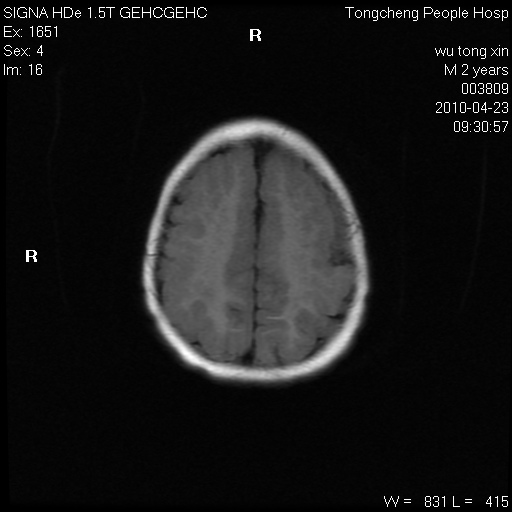

以下是引用赵物学在2010-4-25 12:43:00的发言:[br]巨脑回[br]侧脑室后角低密度影考虑hie或肾上腺脑白质营养不良?[br][br][本贴已被 赵物学 于 2010-4-25 12:51:28 修改过]

以下是引用gaoxiao在2010-4-25 16:54:00的发言:[br]巨脑回畸形。脑白质髓鞘化不良

以下是引用pujunzhi在2010-4-25 21:35:00的发言:[br]考虑 1双侧大脑皮质发育不良 2轻度脑积水 3双侧脑室后角旁片状长t1长t2信号,需继续观察,因为正常小儿此处脑白质的髓鞘化时间可以延迟到4-6岁,才显示正常。